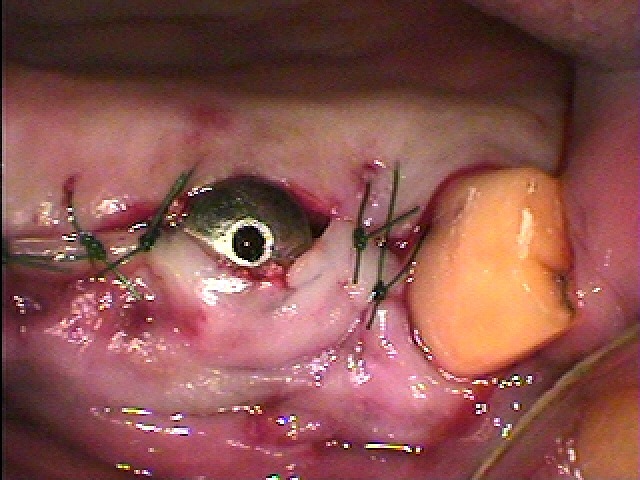

このようにインプラントを埋入していきます

GBRによる骨造成を行っています

縫合して終了となります